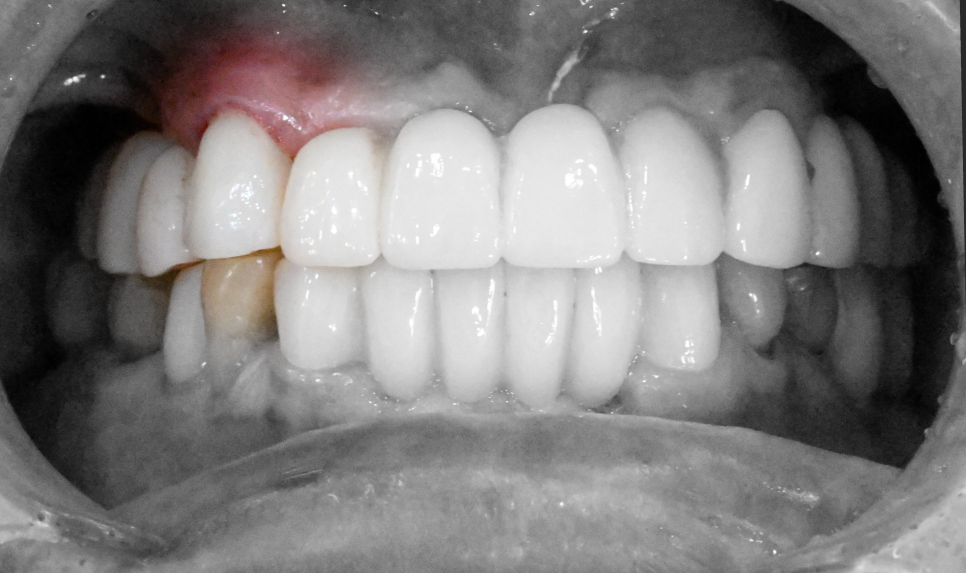

사진처럼 치아머리 부분이 온전히 파절된 경우,

그대로 보철을 씌우기엔 한계가 있습니다.

보철과 지대치가 연결되는 부분이

어느 정도 확보되어야 유지에 별다른

문제가 없기 때문이죠.

잇몸 윗쪽으로 지대치가 어느 정도

확보될 수 있도록 [치관확장술]을

적용해 볼 수 있습니다.

잇몸을 절개하여 치아머리 부분을 확보하는 시술로

지금처럼 파절된 범위가 넓을 때 적용해 볼 수 있으며,

앞서 당산동 치과 에서 설명드린 치관확장술 과정을 통해

앞니 머리 부분 지대치를 어느 정도 확보한 후,

크라운을 씌워 치료를 마무리할 수 있습니다.